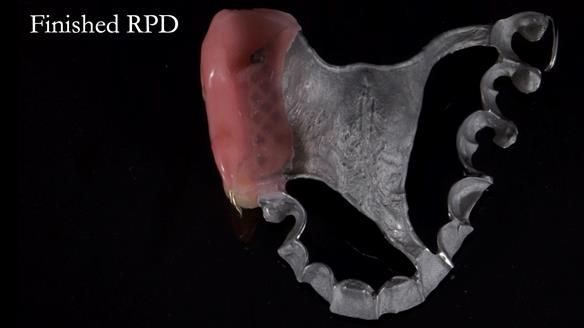

Welcome to Newsletter 64. I'll walk you through the process of providing a Mk 2 metal-based partial denture (RPD), for Ian a retired Veterinary Surgeon aged 78. The RPD was made at an increased vertical dimension and acted as an occlusal stabilisation splint - reducing the wear and bite force on the remaining natural teeth.